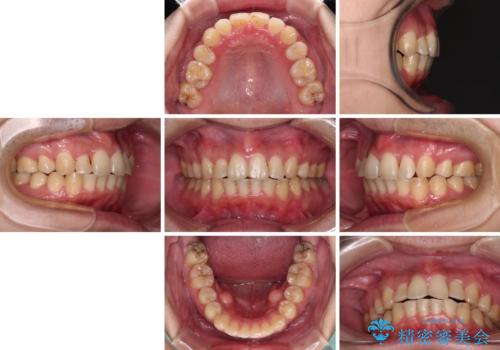

強い咬み込みですり減った前歯 デコボコを抜歯矯正で整える

咬合力が非常に強く、抜歯したスペースがなかなか閉じないであろうことは予想できましたが、思っていた以上に期間がかかりました。

前歯のすり減りも著しかったため、仕上げの位置の調整にも期間を要しました。